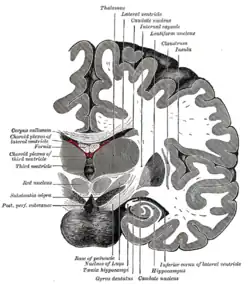

Coronal section of brain immediately in front of pons.